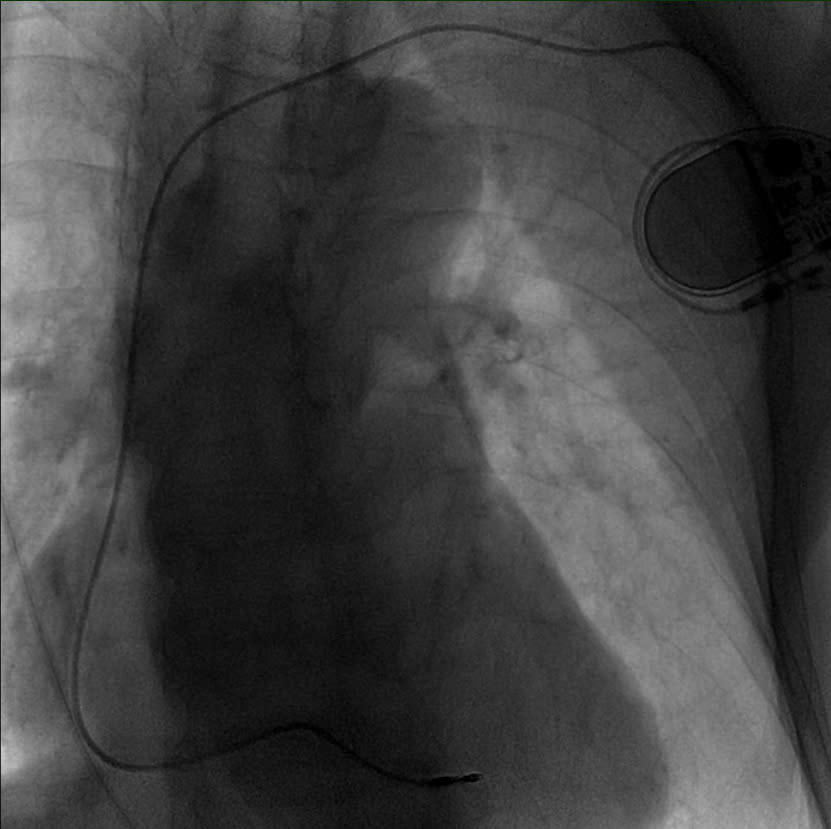

Chụp kiểm tra máy tạo nhịp trước khi kết thúc

Phương pháp chọc tĩnh mạch dưới đòn có dẫn đường bằng chụp tĩnh mạch dưới màn hình tăng sáng

Để đảm bảo an toàn tối đa, ekip đã lựa chọn phương pháp chọc tĩnh mạch dưới đòn có dẫn đường bằng chụp tĩnh mạch dưới màn tăng sáng (fluoroscopy). Đây là kỹ thuật hiện đại, cho phép định vị chính xác vị trí tĩnh mạch trong những cơ địa khó, giảm thiểu nguy cơ tổn thương mạch và các biến chứng khác. Tư thế và kỹ thuật chọc kim cũng được điều chỉnh linh hoạt để phù hợp với tình trạng gù vẹo của bệnh nhân.